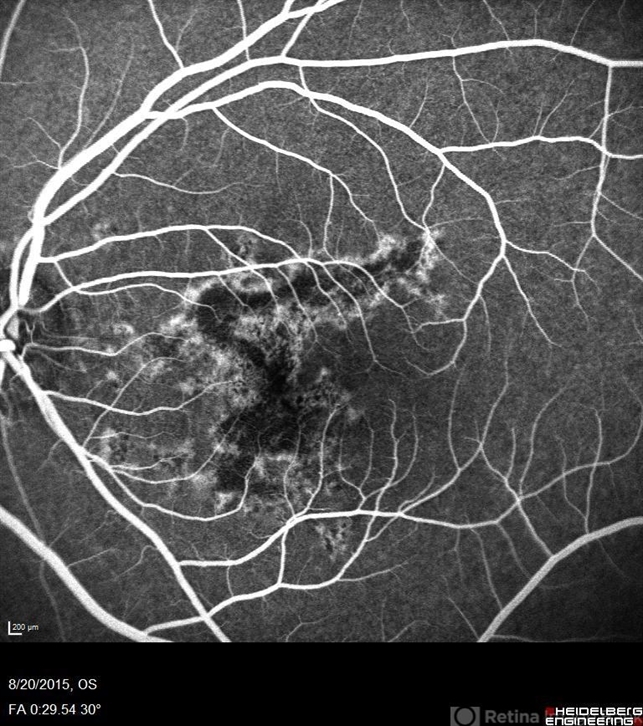

- macula serpiginous choroidopathy

- Phylicia Yanna, Retina Eye Center, Eye Associates of Northeast Louisiana

- Heidelberg Spectralis

- Fluorescein angiography of an 18-year-old with macular serpiginous choroidopathy.